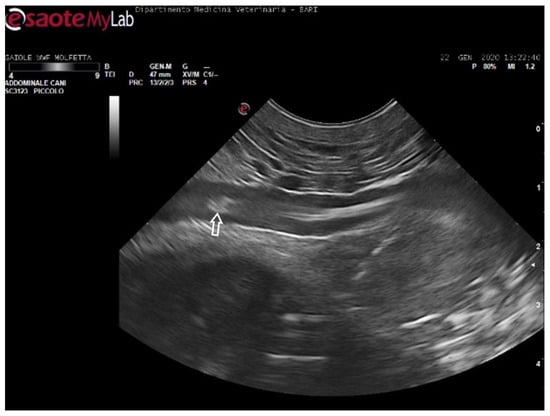

During the ultrasound examination of the seven animals in which no emboli were detected, all the accessible vessels through the acoustic windows were clearly visualized. Blood flow was easily detectable with Color Doppler. From both prefemoral acoustic windows, the renal and iliac arteries were easily distinguishable, along with their blood flow (Figure 4).

Figure 4.

Ultrasound scan from the left prefemoral window reveals normal vascular flow within the iliac artery (the white arrow indicating its wall).

From the left prefemoral acoustic window, the liver parenchyma could be distinguished, and the blood flow in the relevant vessels was often observable.

Ultrasonography also provided clear views of the intestinal loops with their vascular structure and the stomach. The ventral cervical window allowed for the distinct visualization of the trachea and esophagus, with their paths easily traceable. No vascular alterations were evident by ultrasound. The same animals had been categorized as negative by the radiological examinations.